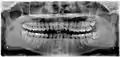

Рентгеновский снимок ретинированного нижнего правого зуба мудрости с горизонтальной ориентацией

Дистоугольно ретинированы верхний левый (изображение справа) и верхний правый (изображение слева) зубы мудрости. Левый нижний зуб мудрости ретинирован горизонтально. Нижний правый зуб мудрости вертикально ретинирован (не идентифицируется на ортопантомограмме).